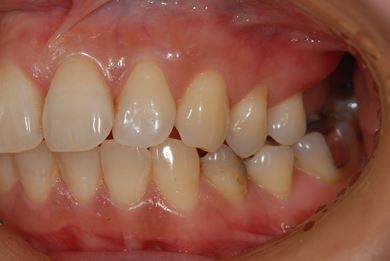

インプラントの症例写真 IMPLANT

骨再生インプラント治療+セラミック治療+歯肉歯槽骨整形

| 性別/年齢 | 女性 / 42歳 | ||||||||||||||||||||||||||||||||

| 主訴 | インプラント治療を受けたい。 | ||||||||||||||||||||||||||||||||

| 治療方針 | 左上奥欠損部分をインプラント治療にて機能的・審美的回復を行う。 | ||||||||||||||||||||||||||||||||

| 治療内容 | インプラント2本(ソケットリフト)、メタルボンドセラミック3本(メタルボンド用土台1本)、歯肉歯槽骨整形 | ||||||||||||||||||||||||||||||||

| 総治療費 | 1,227,713円 | ||||||||||||||||||||||||||||||||

| 治療期間 | 11ヶ月 |